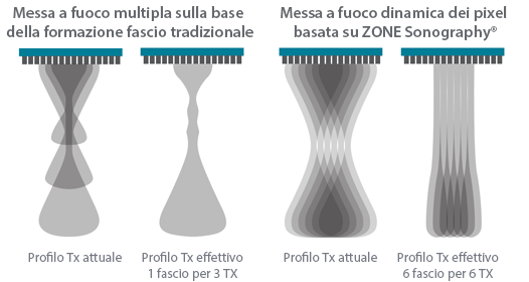

Fin dalla sua fondazione Mindray esplora continuamente nuovi modi per migliorare l'affidabilit├Ā diagnostica. Equipaggiata con la pi├╣ rivoluzionaria tecnologia ZONE Sonography?, la nuova piattaforma ZST+ di Resona 7 porta la qualit├Ā dell'immagine ecografica ad un livello superiore con l'acquisizione per zone e l'elaborazione dei dati canale.